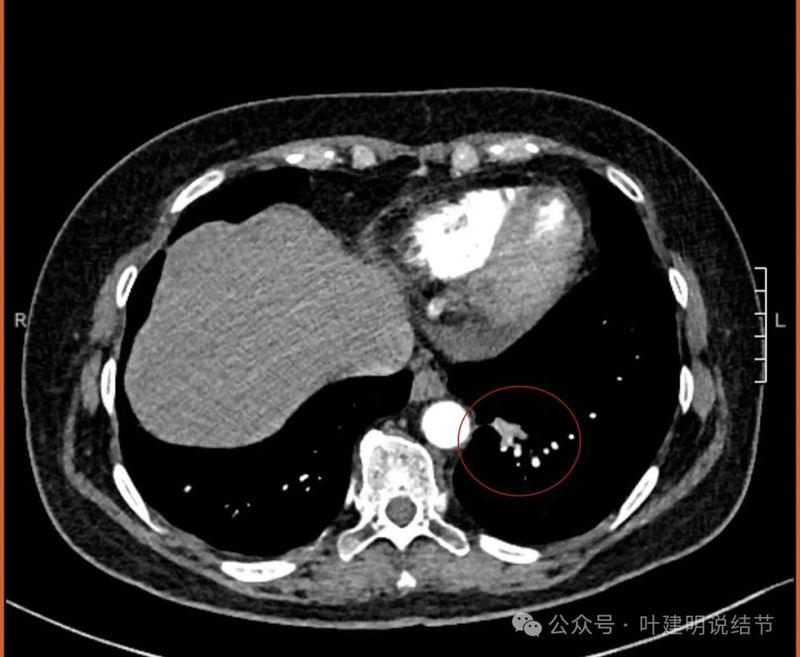

纵隔窗见有明显实性成分,磨玻璃成分不可见,走行血管也明显。

纵隔与肺门没有见到显著增大融合要考虑转移的淋巴结。